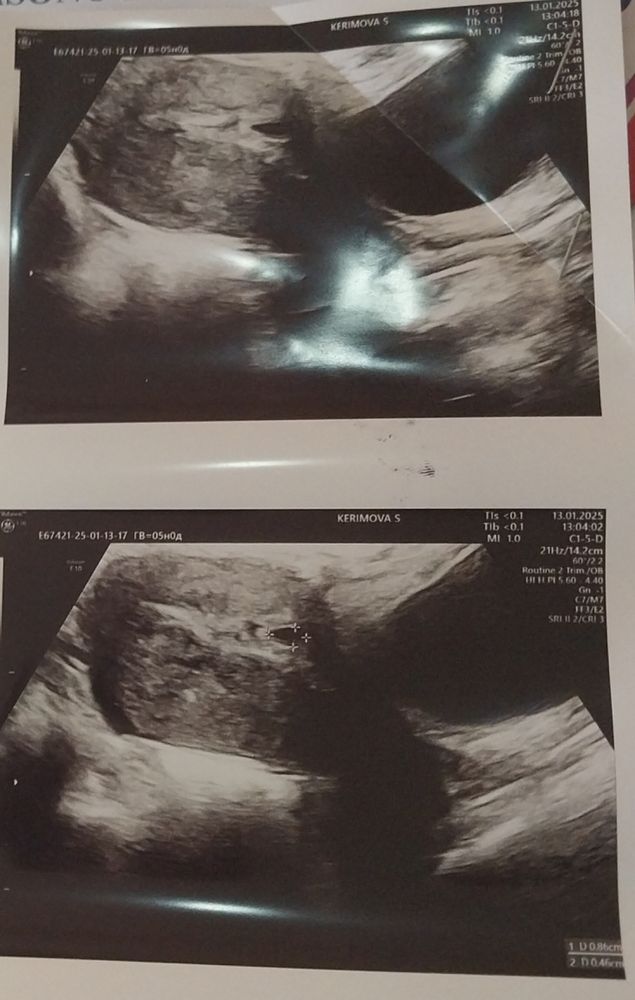

Результаты: УЗИ, КТГ, доплера, скринингаПишу и плачу, иначе не получается 😢😭Сегодня ровно 5 недель акушерских, пошла к гинекологу и на узи соответственно. Узистка сперва не увидела ничего, потом заметила всё-таки и в заключении написала: в полости матки в нижней части за рубцом визуализируется плодное яйцо 8*4мм. Сказала, что такую беременность лучше прерывать, но если я хочу могу придти на контрольное узи через 7-10 дней. Гинеколог тоже сказала лучше прервать беременность. У меня 3 дочери, понимаю разумом, что риск большой, но с другой стороны снова проходить через этот ад в виде аборта не хочу, первая беременность была неразвивающейся.... Может ли что-то изменится через неделю или узи быть ошибочным?